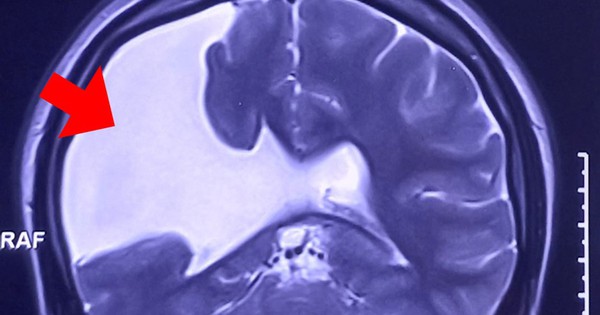

Tại Bệnh viện Đa khoa Tâm Anh, kết quả chụp MRI 3 Tesla (loại máy thế hệ mới nhất) cho thấy não chị N. có một khe nứt lớn kéo dài từ vỏ não đến não thất nằm bên bán cầu não phải.

Chị N. bị nứt não bẩm sinh từ nhỏ nhưng không biết, đến nay vết nứt mở rộng, gây động kinh, co giật nghiêm trọng. Nhiều năm qua, chị điều trị co giật, động kinh với liều thuốc cao nhất nhưng không có kết quả.

“Đa số trường hợp dị tật nứt não nhỏ không làm gia tăng áp lực nội sọ đến mức phải can thiệp. Trường hợp của chị N. là đặc biệt, vết nứt não mở rộng, dịch não tủy tràn vào làm gia tăng áp lực nội sọ, chèn ép lên bề mặt vỏ não gây động kinh. Giải pháp tối ưu là phẫu thuật giải áp, sau đó tiếp tục theo dõi, điều trị bệnh động kinh” – bác sĩ Sĩ nhấn mạnh.